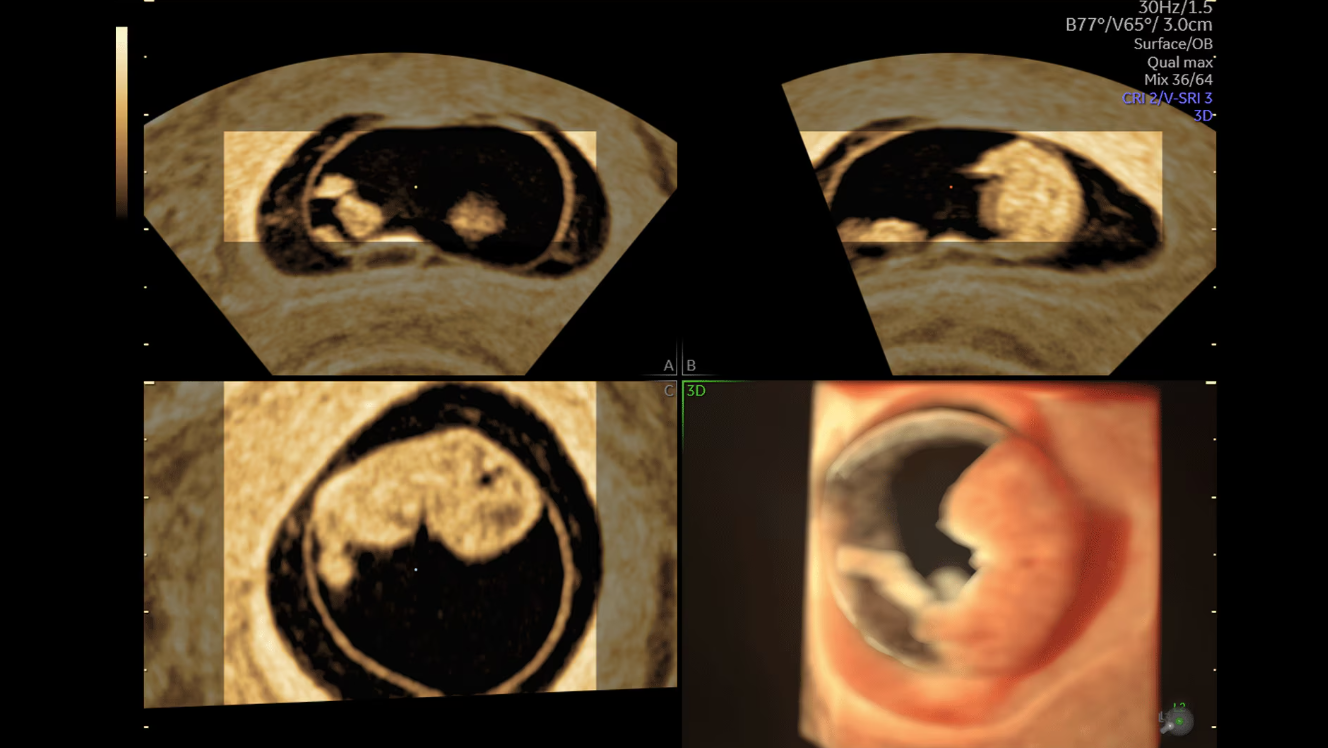

8-недельный эмбрион с HDlive Studio

Профиль плода на 21 неделе

Лицо плода с HDlive studio